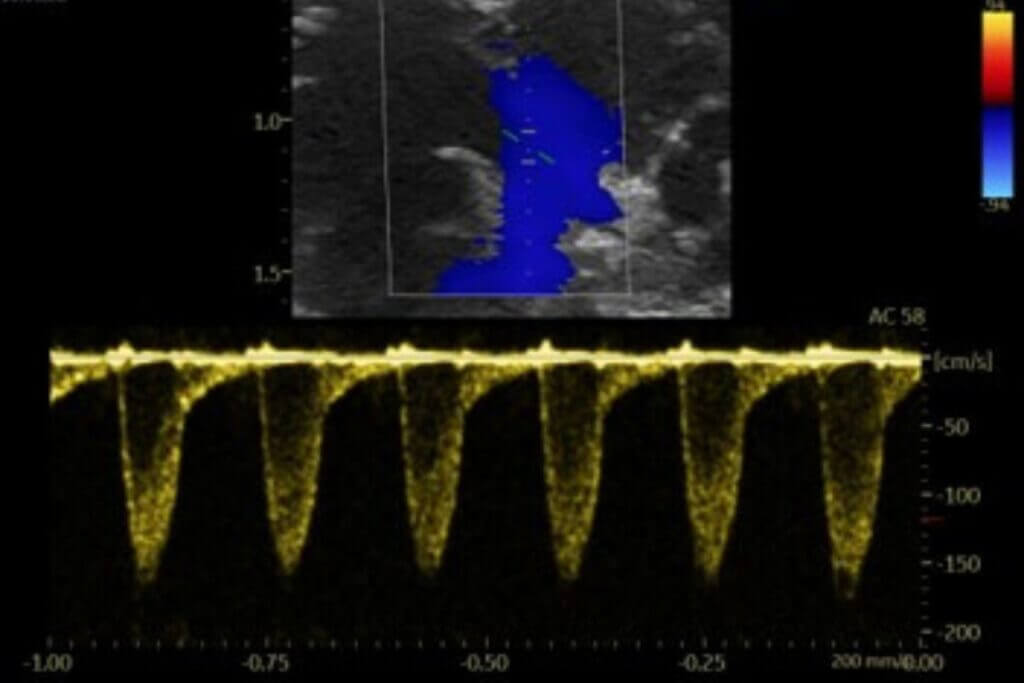

Our platform enables the direct evaluation of therapeutic candidates in both HFrEF and HFpEF models, integrating comprehensive assessments of left ventricular function by echocardiography, cardiac remodeling, and cardio-renal-metabolic interactions.